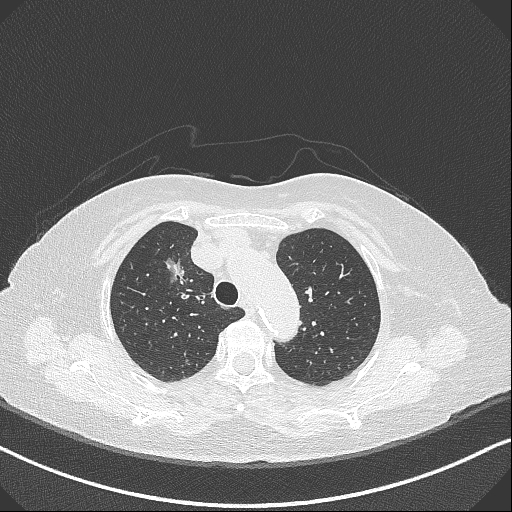

陳婆婆于4月29日因檢查發(fā)現(xiàn)肺占位性病變4+月入住我科,經(jīng)術(shù)前相關(guān)檢查,手術(shù)切除肺結(jié)節(jié)的指針明確。然而為90歲高齡患者動(dòng)肺結(jié)節(jié)手術(shù),對(duì)手術(shù)團(tuán)隊(duì)是一個(gè)巨大考驗(yàn)。

主刀醫(yī)師刁明強(qiáng)主任為此聯(lián)合麻醉科、心血管內(nèi)科、重癥醫(yī)學(xué)科等相關(guān)科室于術(shù)前行多學(xué)科會(huì)診(MDT),最終決定采用國際先進(jìn)的“Tubeless”單孔胸腔鏡技術(shù)——術(shù)中不插氣管插管、尿管等管道,最大限度減少創(chuàng)傷。在韓佳副主任醫(yī)師為首的手、麻團(tuán)隊(duì)的精心配合下,于5月7日順利的進(jìn)行了手術(shù)治療,手術(shù)過程精準(zhǔn)高效,出血量極少,術(shù)后精神極佳,能夠正確咳嗽咳痰,行呼吸功能鍛煉,術(shù)后第一天便下床活動(dòng),但因?yàn)槭中g(shù)創(chuàng)傷以及年齡過大,下床活動(dòng)偶感傷口疼痛,些許氣緊,行走不便,需要家屬陪護(hù)照看,但已經(jīng)刷新了高齡患者肺手術(shù)的康復(fù)記錄。